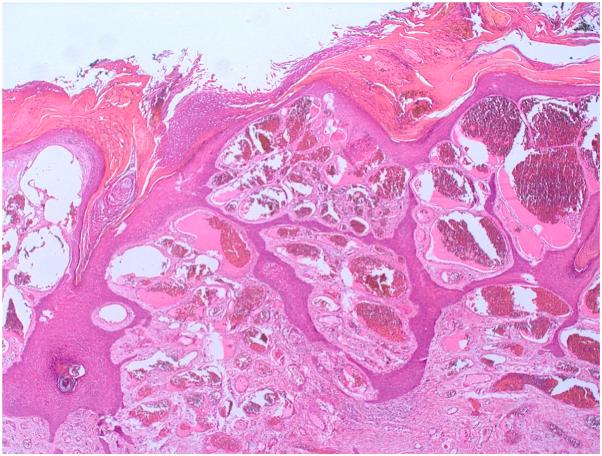

Verrucous venous malformation: A case report of a rare entity with dermatoscopic features.

JAAD Case Rep. 2024 Nov 10;60:69-72. doi: 10.1016/j.jdcr.2024.10.022. eCollection 2025 Jun.

DOI:10.1016/j.jdcr.2024.10.022

PMID:40353112

原文链接:https://pmc.ncbi.nlm.nih.gov/articles/PMC12063020/